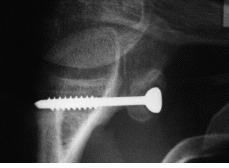

Ninguno de los pacientes intervenidos presentó nuevas luxaciones después de la cirugía. El déficit medio de rotación externa comparando las dos extremidades fue de 9° (* = 6°) y no hubo diferencias significativas en cuanto a rotación interna y la antepulsión. Un 60% de las pastillas estaban en el tercio inferior, el 20% en el tercio medio y otro 20% en el superior (Fig. 1). El 39% estaban enrasadas con el margen anterior de la glena, el 22% se habían colocado externas (Fig. 2) y el 39% se encontraban en situación demasiado medial (Fig. 3). En tan solo uno de los casos se utilizaron dos tornillos para fijar la pastilla ósea. En el resto se utilizó un tornillo pero sólo en la mitad de los casos éste atravesaba las dos corticales (Fig. 4). El tipo de tornillo más utilizado fue el maleolar (n = 18), y en tres casos se implantó un tornillo de escafoides. La mitad de las pastillas mostraban signos de consolidación, mientras que en el resto, el 21% habían migrado (Fig. 5) y el 28% se mantenían en posición merced a una unión fibrosa (Fig. 6). En ningún caso se evidenció osteolisis de la pastilla. Tan solo dos pacientes cumplían todos los parámetros radiográficos ideales. Ningún paciente requirió ser reintervenido por complicaciones clínicas posteriores, o por migración o rotura del tornillo. No se detectaron lesiones vasculonerviosas ni infección postoperatoria en ningún paciente.

Figura 4. Proyección de outlet. Tornillo de escafoides atravesando las dos corticales.